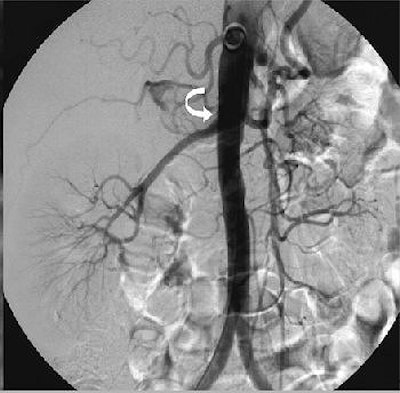

| Fifty-six-year-old healthy female living renal donor with stenosis of ostium of right renal artery. Above, volume maximum-intensity-projection MR angiography image using subtraction technique shows stenosis of ostium of right renal artery (arrow). Below, axial maximum-intensity-projection MR angiography image shows anterior origin of right renal artery with ostium stenosis (arrow). |